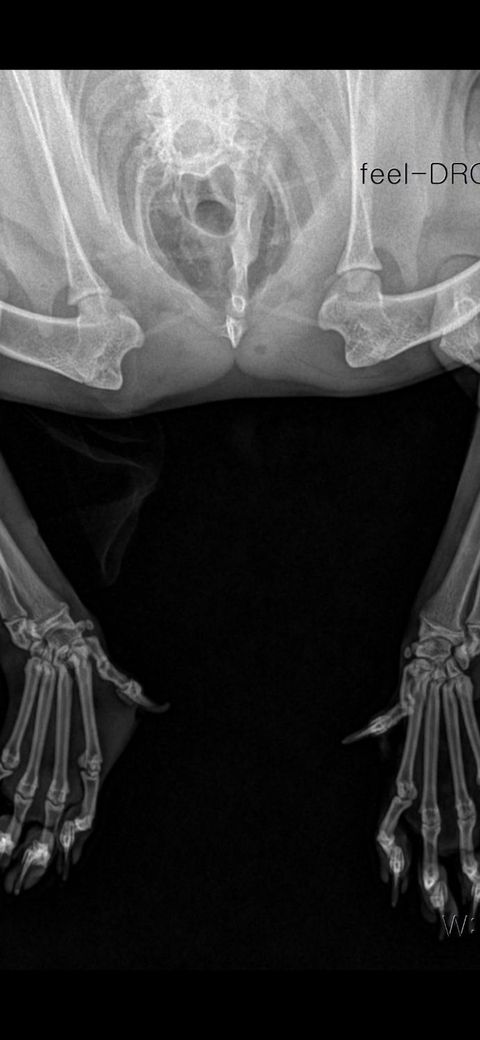

탈구 된 직후 엑스레이 사진